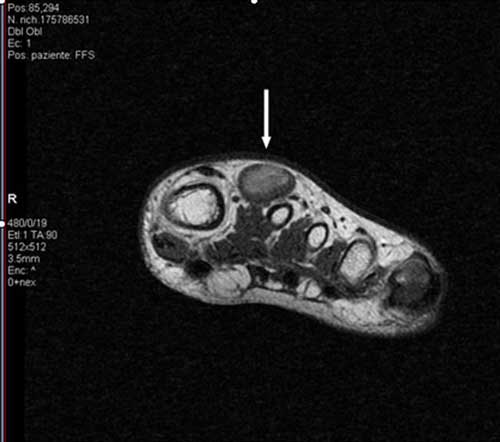

Figura 3. Presenza di flusso in parete. � stata effettuata una RMN con contrasto con acquisizioni multiplanari T1 e T2 pesate anche con tecnica di soppressione del grasso, con il rilievo di una formazione ovalare di 16 x 12 x 20 mm a margini regolari con iperintensit� di segnale centrale nelle pesate T1 e T2 dipendenti, e componente periferica sottile che subisce enhancement contrastografico, in apparente continuit� anatomica con struttura vascolare del fascio vascolo-nervoso dorsale, ascrivibile, in primis, a formazione vascolare o patologia vascolare dilatativa trombizzata (Figure 4, 5 e 6). ![]() |

Figura 4. Angio-RMN Scansione assiale T1 pesata SE. |